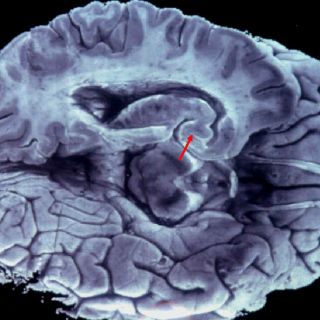

Llaman a fomentar donación de cerebros para investigar Alzheimer

El coordinador del Banco Nacional de Cerebros del Centro de Investigación y Estudios Avanzados del IPN, José Luna Muñoz, reveló que en 20 años se han captado 200 cerebros, de los cuales sólo 17 han tenido alzheimer.

En conferencia de prensa expuso que para investigar más sobre esta enfermedad se requiere de tejido cerebral y para qué sea óptimo, no deben pasar más de 24 horas de que el donante haya fallecido.